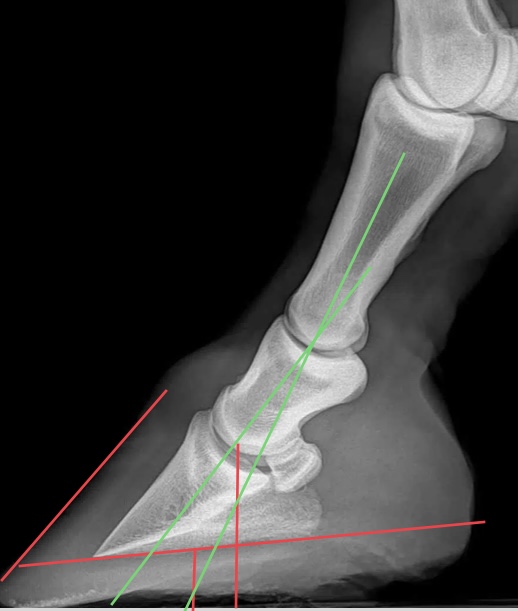

Når bildene er tatt, kan de behandles digitalt, før de oversendes til eier og hovslager. Det er spesielt interessant å benytte måleverktøy ved behandling av bildene, som en veiledning på hvordan hoven bør korrigeres. Ved problemer som for eksempel forfangenhet, vil også noen målinger kunne gi en pekepinn om alvorlighetsgrad og prognose.

Flere målinger kan være akutelle, dette avtales gjerne mellom hovslager og veterinær. Noen eksempler kan være hovvinkel, lengde på hovvegg i tå, lengde på hovvegg i drakt. Såletykkelse, hovveggstykkelse, hovbensvinkel og overrullingspunkt.